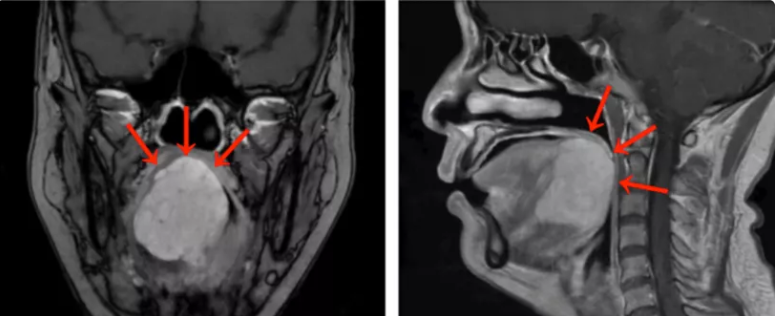

“刘女士的舌根部肿物达到5厘米,几乎占据整个舌根部并向口咽腔突出。”首届“广州实力中青年医生”、中山大学肿瘤防治中心头颈外科门诊宋明主任医师表示,MRI检查提示舌根肿块巨大,范围约47毫米×46毫米×45毫米,向前侵犯部分舌体,向下侵犯部分口底肌群。活检病理诊断考虑为舌根腺样囊性癌。